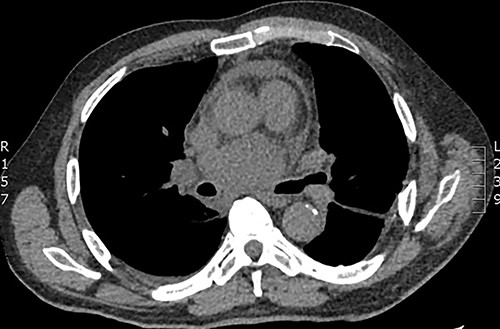

Our first case was a 66-year-gentleman male with an incidental large subcarinal mass identified on contrast enhanced CT scan during pre-operative investigations for an infra-renal abdominal aortic aneurysm. He had previously undergone left thoracotomy and decortication following parapneumonic empyema 20 years ago. Contrast enhanced CT thorax revealed a 6 × 5 × 4-cm subcarinal mass measuring 65-Hounsfield unit and a 6-cm infrarenal aneurysm. He was referred to the respiratory physicians for further investigations of this mediastinal mass. Following discussion at the multidisciplinary meeting (MDT), there were concerns of mediastinal lymphadenopathy and he underwent EBUS, which showed a heterogeneous echogenic lesion in keeping with solid/semi-solid with multiple foci of calcium within it. EBUS guided biopsy revealed gel like material raising concerns of a suspicious mass. The infrarenal aneurysm was to be kept under surveillance. Five days following the procedure the patient presented to hospital in septic shock. Repeat CT imaging demonstrated an enlarged cyst 7.6 × 6.3 × 5.5-cm compressing the right pulmonary artery with a tense pericardium and pleural effusion (Fig. 1). The patient was haemodynamically unstable with cardiac tamponade and was admitted to intensive care for inotropic support and stabilisation prior to undergoing emergency surgery. Right posterolateral thoracotomy was performed, which revealed pyopericardium and purulent material with dense adhesions in the subcarinal region and its surrounding structures. The pericardium was opened, and the cavity irrigated with saline. The cyst was completely de-roofed and excised as much as possible. Copious washout was performed, and multiple drains were inserted. The patient returned in a stable condition to intensive care where he progressed satisfactorily and later recovered on the eventually discharged following completion of intravenous antibiotic therapy 21 days after admission. Histology demonstrated appearances consistent with infected bronchogenic cyst. Microbiology demonstrated pus cells with no growth on culture.

Axial CT demonstrating large subcarinal mass and pericardial effusion.